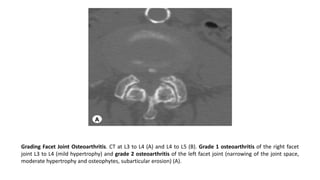

Grading Facet Joint Osteoarthritis. CT at L3 to L4 (A) and L4 to L5 (B). Grade 1 osteoarthritis of the right facet

joint L3 to L4 (mild hypertrophy) and grade 2 osteoarthritis of the left facet joint (narrowing of the joint space,

moderate hypertrophy and osteophytes, subarticular erosion) (A).

Grade 3 osteoarthritis of the right facet joint L4 to L5 with joint space

narrowing, hypertrophy of the articular processes, large osteophytes

and subarticular bone erosions (B).